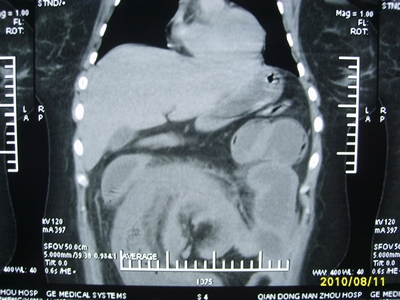

5天前突发腹痛剧烈难忍,伴解淡血水样便。近一天来腹痛缓解,没有明显的腹膜炎的体征。今天照的腹部ct。从ct上看感觉是一个绞窄性肠梗阻,但是现在没有腹痛。不好解释

要有麻烦了,感觉小肠有套叠还有扭转改变,估计部分已有坏死。

高位肠梗阻(不全性),原因小肠(空肠)扭转,肠壁水肿增厚,成年人肠梗阻要排除合并占位,建议手术。

绞窄性肠梗阻_肠管套叠 扭转,肠壁明显水肿。

病人现在没有腹痛。怪了。从影像上来看。确实是绞窄了。但是没有腹痛。没有明显的腹膜炎的体征。确实有不好解释。难道是坏死了。反而不痛了。怪怪怪

支持绞窄性肠梗阻,肠壁明显水肿并见有多发小泡状积气--肠坏死

考虑绞窄性肠梗阻并肠坏死。